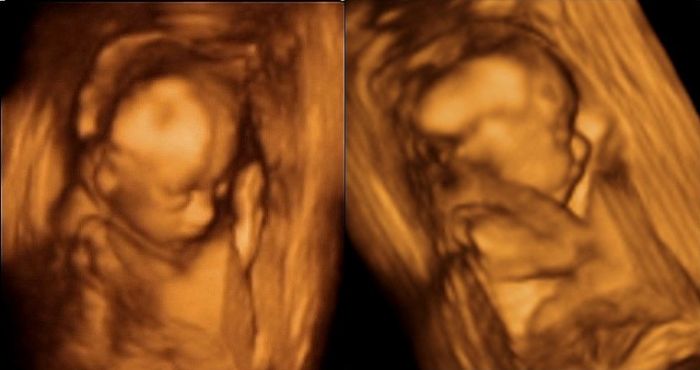

Ahoj holky,tak máme 3D UZ za sebou,ale teda čekala jsem od toho asi víc,po tom co sem tu viděla i opravdu nádherné a detailní fotky..

Doufala jsem,že ta tvářička bude vidět líp,ale to prý bývá nejhezčí až tak kolem 28tt..

Hlavně teda mrňous totálně nespolupracoval,ale co by jsme chtěli,když má svojí hlavinku a včera ukázal že nejspíš pěkně tvrdohlavou..

Na začátku spinkal,tak to trošku šlo,až na to,že ležel z profilu...Když už se vzbudil,odmítal dát ručičky pryč z obličeje a když už se nám pak po několika převaleních a dřepech podařilo ho trošku probrat,začalo naopak rodeo..

Měla sem pocit,že chytil jakýsi záchvat zuřivotsi,protože měl pusinku dokořán jakoby brečel nebo křičel,ručičkama tam mával zlostně kolem hlavičky a hlavičkou prudce otáčel ze strany na stranu,nahoru dolu až mě ho bylo líto,když sem viděla jak vyvádí..

Nakonec mu chudince došla trpělivost,tak usnul a otočil se úplně zády s rukou za hlavou,takže nám dal jasně najevo kde mu už asi jsme a ať ho necháme být..

Taky teda ještě asistentka říkala,že když je placenta na přední straně,je tam ta viditelnost prý mnohem horší,než když je uložená vzadu za miminkem a u nás to k tomu ještě komplikoval fakt,že ty placenty mám dvě,přesně naproti sobě a mrňous byl mezi ně dost natěsno..

Takže asi tak no...Nemůžu říct,že to nebyl hezký zážitek a vzpomínka,aleza ty peníze sem asi čekala trošku lepší výsledek..

POsílám pár 3D fotek + 2D fotku dvou placent..

Jé Baruš,to je hezké,jak spinká s ručkama u hlavičky,vypadá spokojeně,řekla bych,a možná že nekřičí,ale usmívá se.No asi tomu dám ještě jednu šanci a kolem 29 tt zajdu znova.

Adri,na te jedne vypadá opravdu jako by se smál..

ALe pak na te další zase má opravdu vzpurný výraz..